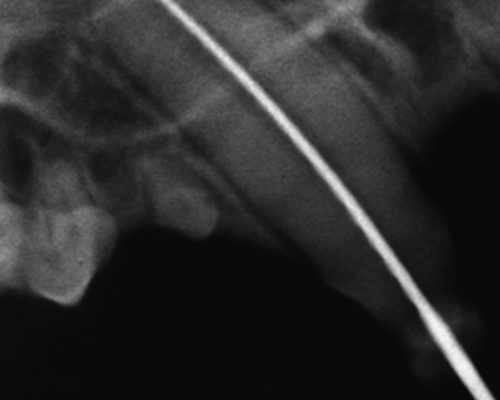

치아 방사선 촬영

- 치과 진료 시 가장 중요한 검사는 치아 방사선 촬영입니다.

우리가 눈으로 보는 치아 부위는 전체 치아의 일부이기 때문에 잔존 치아를 체크하기 위해서는 치아 방사선 검사가 반드시 진행되어야합니다.